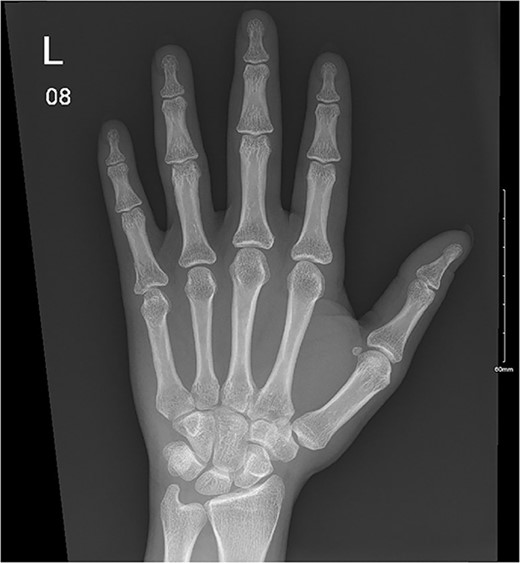

A 28-year-old female came to the emergency room (ER) following an MVA with airbag-deployment 5 days before presentation. Examination revealed tenderness at the base of the proximal fifth finger. The ROM of the affected digit was limited, but the neurovasculature as well as flexor digitorum profundus and flexor digitorum superficialis function were intact. X-ray of the hand showed a minimally displaced fracture at the base of the proximal fifth phalanx extending into the articular surface (Fig. 5). The decision was made to manage the patient conservatively by applying an ulnar gutter splint, which was then changed to a volar splint when the patient was followed-up in the clinic a week later. When the patient was last seen, the patient had limited ROM, and the tenderness had resolved. Imaging showed evidence of ongoing healing (Fig. 6).

Ongoing healing is seen in the distal radius fracture. The fracture line is barely visible.